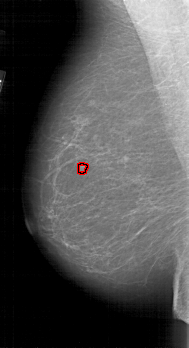

A_1812_1.RIGHT_CC

RIGHT_CC LINES 5491 PIXELS_PER_LINE 2986 BITS_PER_PIXEL 12 RESOLUTION 43.5 NON_OVERLAY

FILE: A_1812_1.LEFT_MLO.OVERLAY

TOTAL_ABNORMALITIES 1

ABNORMALITY 1

LESION_TYPE MASS SHAPE LOBULATED MARGINS MICROLOBULATED

ASSESSMENT 4

SUBTLETY 3

PATHOLOGY BENIGN

TOTAL_OUTLINES 1